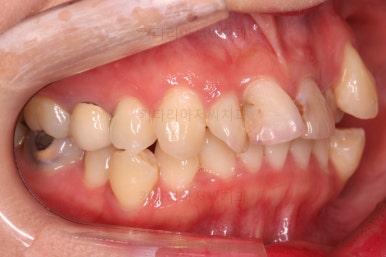

덧니를 개선하기 위해서 추가적으로 작은 어금니를 발치했고요.

이 때 발치하게 된 치아는 가장 약한 치아, 치료가 많이 되어있거나 치료가 필요한 치아 위주로 선택하게 됩니다.

아랫니는 많이 삐뚤긴 했지만 옆라인, 턱의 크기 등 모든 걸 종합적으로 판단해 비발치로 진행하기로 했습니다.

물론 윗니 이미 없었던 치아 부분은 공간을 모아서 임플란트를 하지 않도록 하는게 목표였고요.

옆모습 중간중간 체크해 주고요.

이번 환자분은 옆라인이 애초에 매우 좋으셨기 때문에 입매를 바꾸지 않아야해서 오히려 더 세심한 치료가 필요한 환자분이셨습니다.